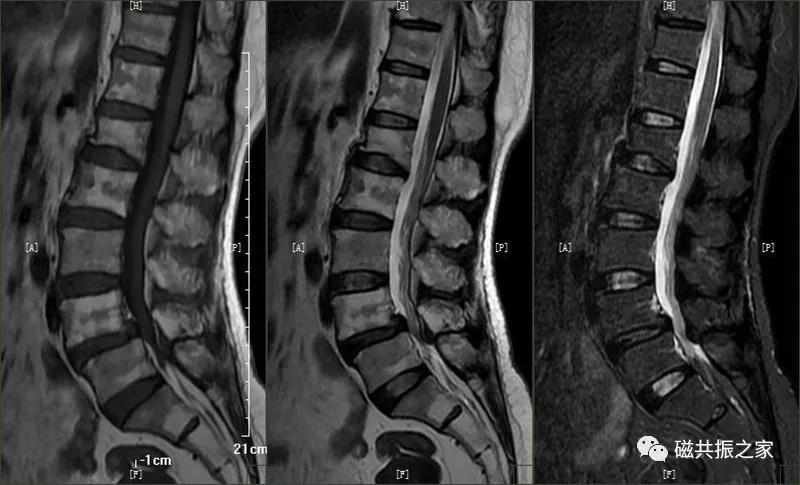

7.腰椎椎体滑脱

脊椎滑脱是指椎体相对下一节椎体向前或后方滑动移位,颈椎、腰椎常见。腰椎以4/5椎体和腰/骶连接部常见。滑脱分为向前和向后滑脱,根据上下椎体的滑动距离分为四度(在矢状位上将椎体上缘分为4等分,对应着1-4度滑脱)。